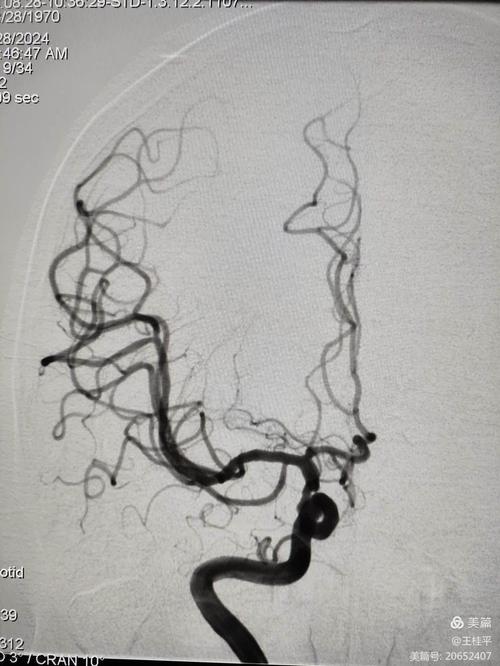

- 机械取栓:这是目前治疗大血管闭塞(如大脑中动脉)的革命性技术,通过介入手术,从大腿根部的血管插入导管,到达堵塞的脑血管处,用支架或网篮将血栓直接取出。时间窗相对较长,可达6-24小时,但越早越好,这是挽救大面积脑梗患者生命和功能的关键手段。